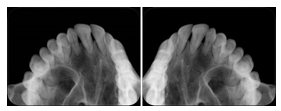

Intra-oral radiography typically involves acquisition of multiple images of various parts of the dentition. Many digital radiographic systems offer customized templates that are used for displaying the images in a study on the screen. These templates may also be referred to as mounts or view sets. The Structured Display Object represents a standard method of encoding and exchanging the layout and intended display of Structured Displays. A structured display object created in this manner could be stored with a study and exchanged with images to allow for complete reproduction of the original exam.

1. A patient visits a General Dentist where a Full Mouth Series Exam with 18 images is acquired. The dentist observes severe bone loss and refers the patient to a Periodontist. The 18 images from the Full Mouth Series along with a Structured Display are copied to a DICOM Interchange CD and sent with the patient to see the specialist. The Periodontist uses the CD to open the exam in his Dental Radiographic Software and consults via phone with the General Dentist. Both are able to observe the same exam showing the images on each user's display using the exact same layout.

Intra-oral Full Mouth Series Structured Display

Figure OO-1. Intra-oral Full Mouth Series Structured Display